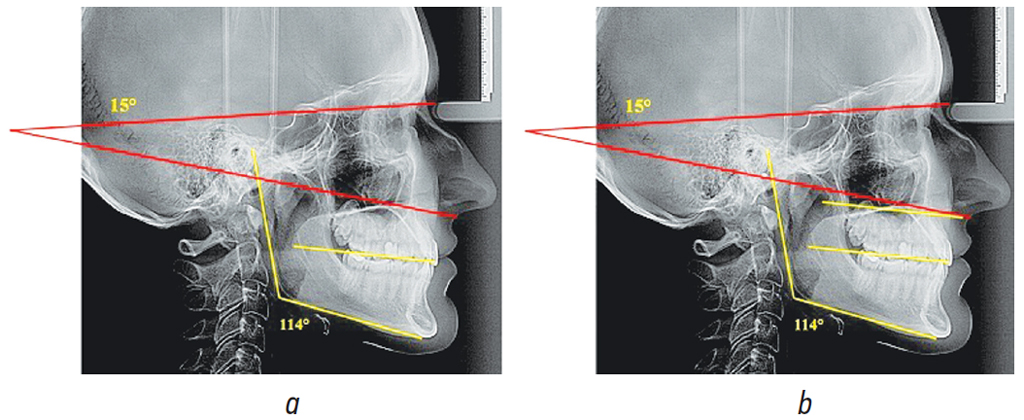

Величина нижнечелюстного угла в среднем по 1-й группе составляла 120,26° ± 1,34°. Величина угла, образованного камперовской горизонталью и плоскостью основания черепа, составляла 15,12° ± 0,39° (рис. 2).

Рис. 2. Особенности расположения линий и углов (а) и сопоставительный анализ камперовской и окклюзионной линий (b) в 1-й группе

Fig. 2. Location of lines and angles (a) and comparative analysis of the Camper and occlusal lines (b) in group 1

Характерная особенность сопоставительного анализа расположения камперовской горизонтали с окклюзионной линией — их расположение практически параллельно. Полученные данные согласуются с мнением большинства специалистов о том, что для определения протетической плоскости в протетической стоматологии рекомендуется в качестве ориентира использовать камперовскую горизонталь.